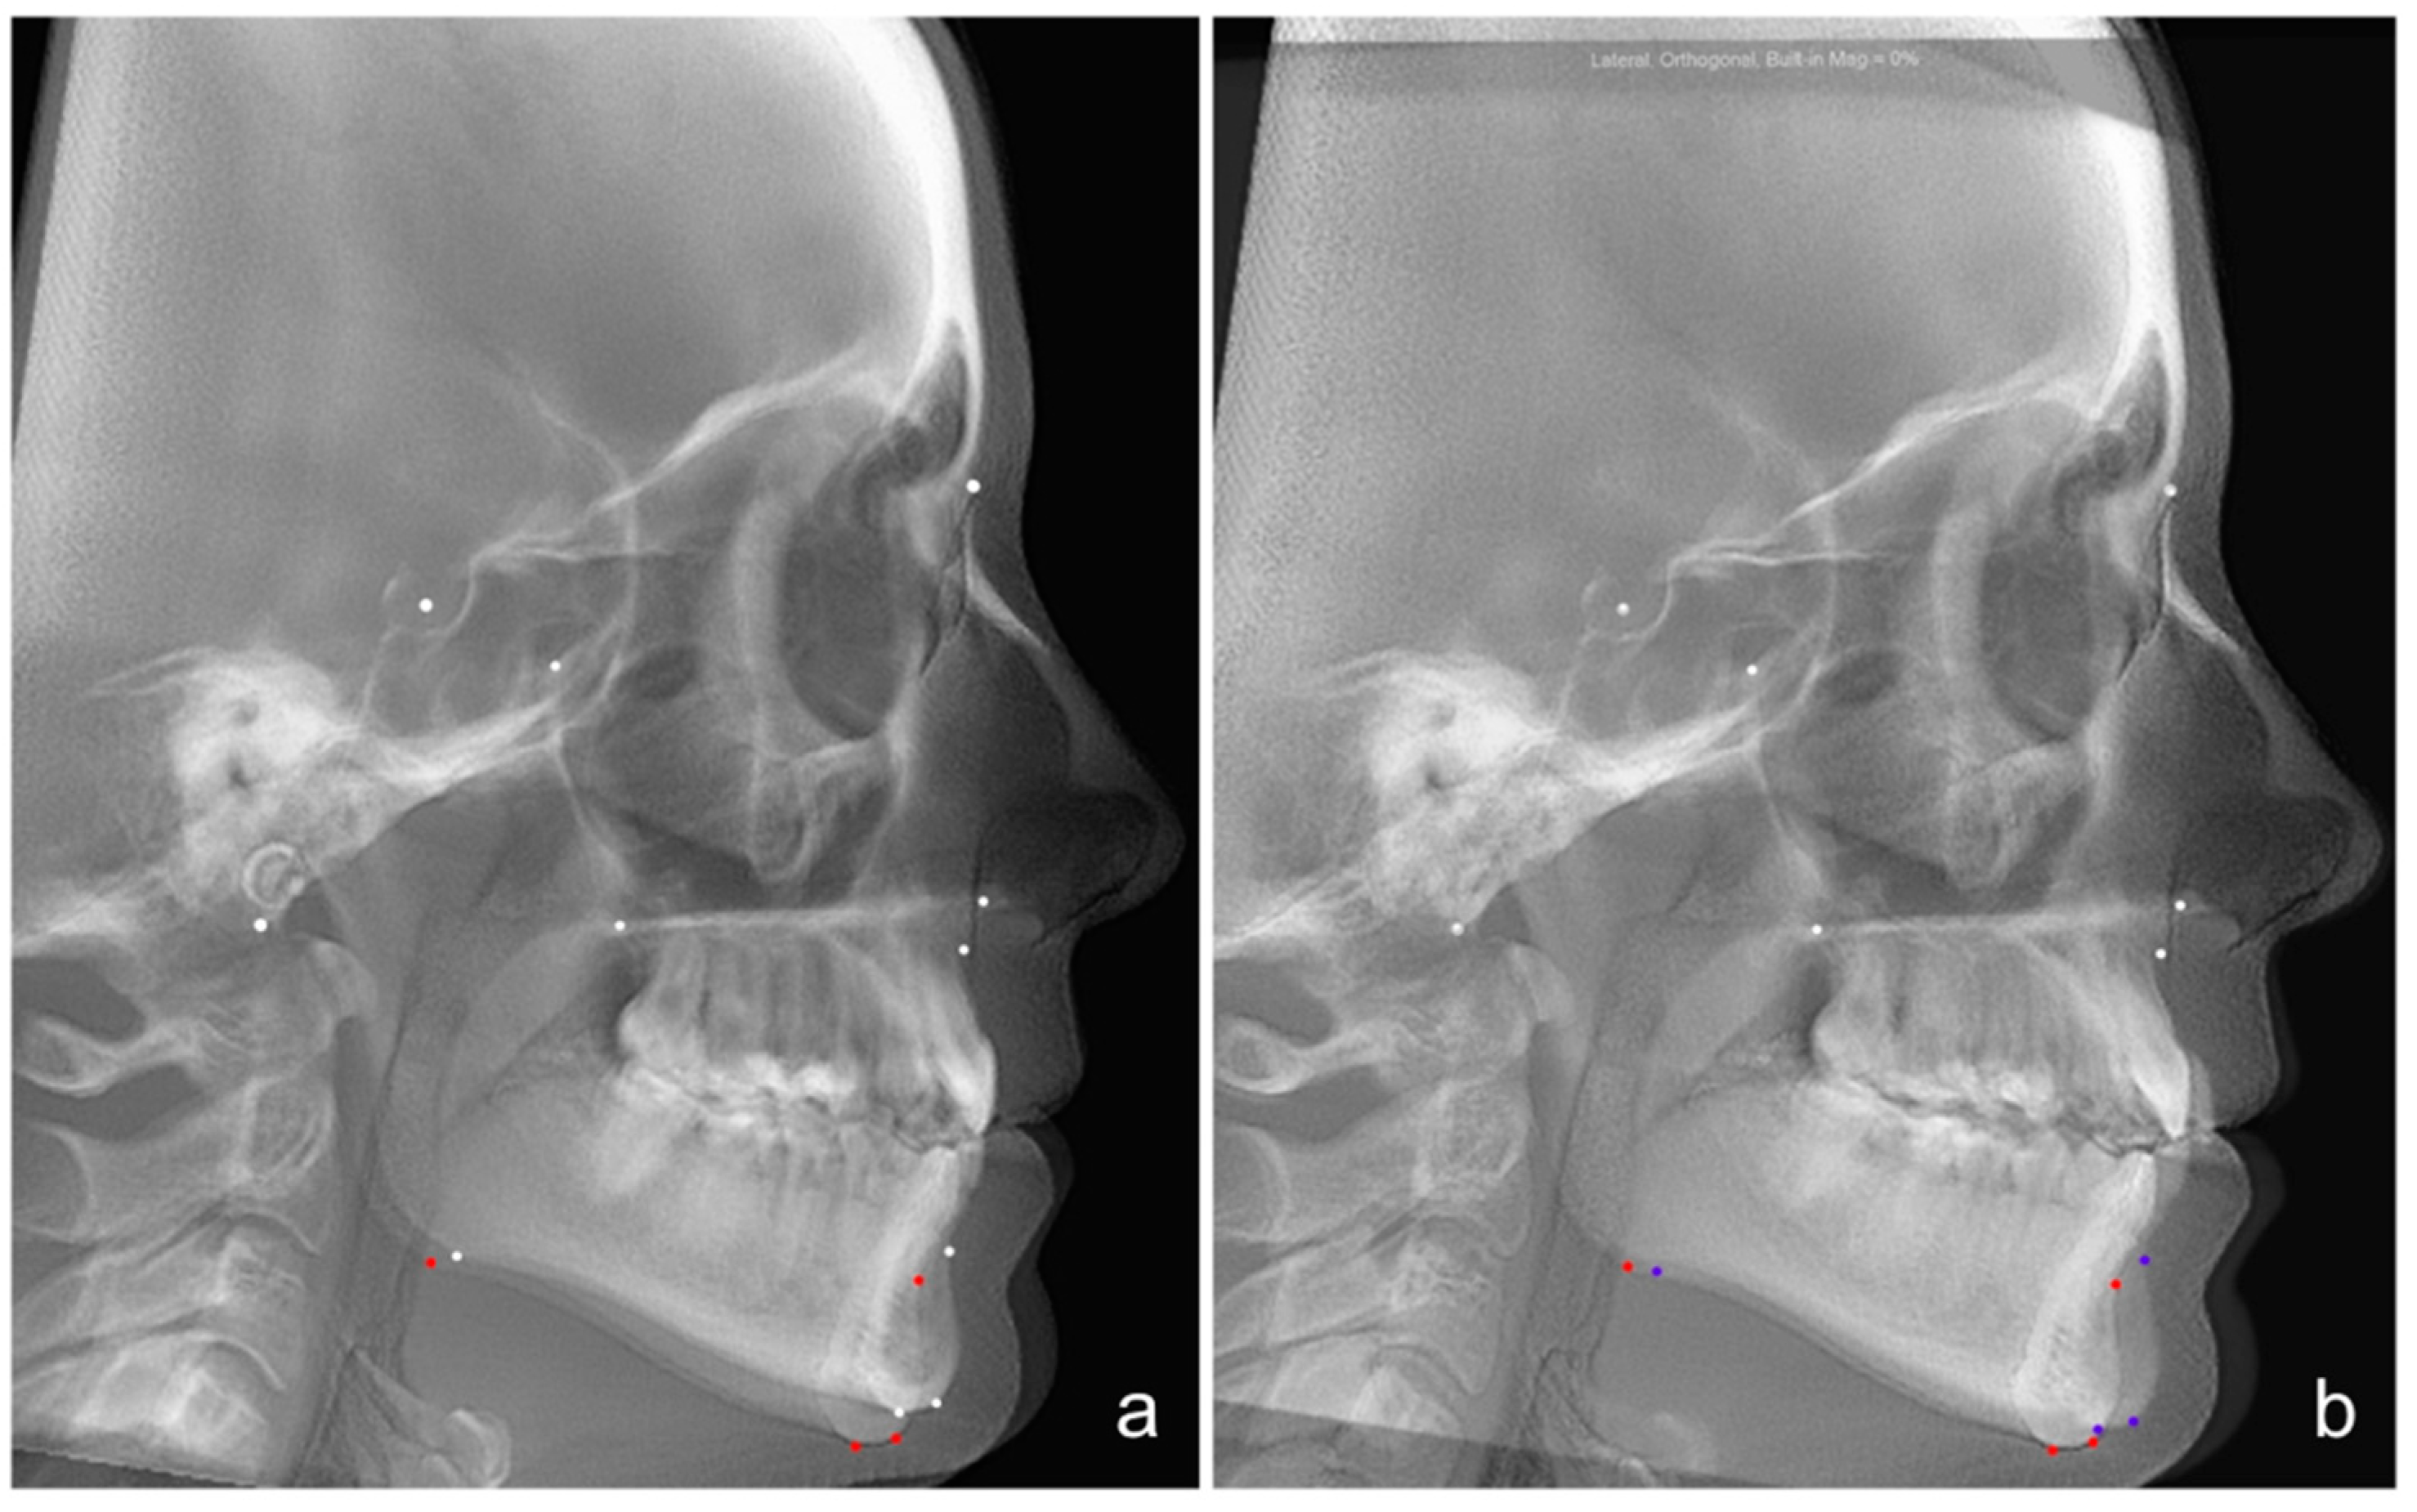

2.4. Cepahlometric Measurements